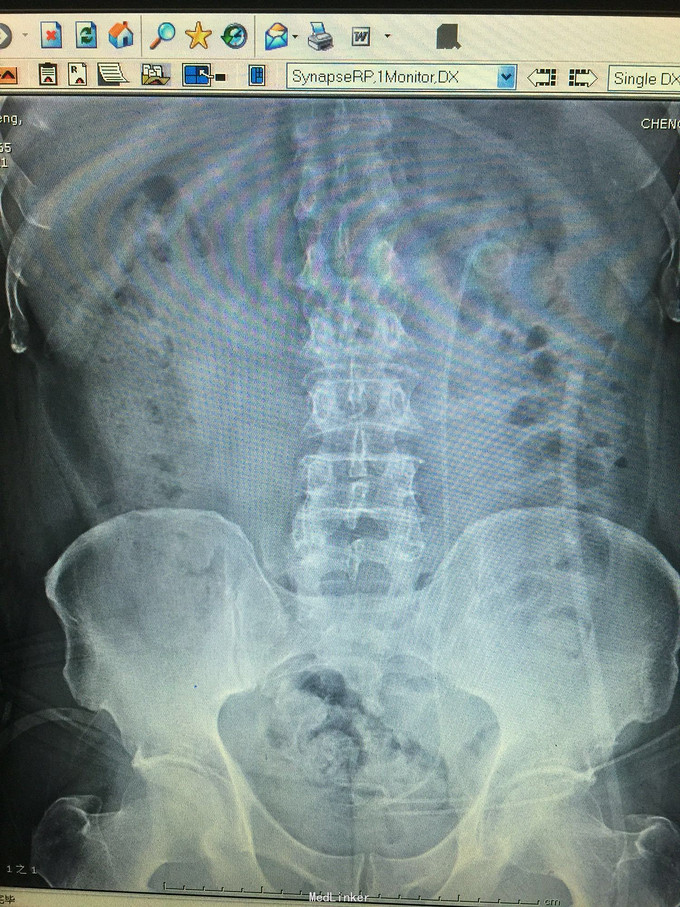

患者男,59岁,因检查发现左肾巨大铸型结石3天入院 病史:患者检查发现左肾结石,无发热,无血尿,无腰痛,食欲,睡眠均正常。

诊断考虑左肾铸型结石。 处理:经皮肾球囊扩张,钬激光加气压弹导碎石,手术顺利,术中术后出血少,术后复查未见结石残留。患者痊愈出院。